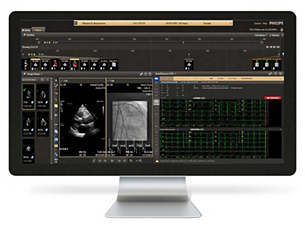

Access multiple modalities from one integrated platform

Enhancements have been made to our core Multi Modality applications including Advanced Vessel Analysis (AVA) and Tumor Tracking (MMTT). New functionality aims to speed workflow and provide additional clinical depth such as glucose measurements on MMTT. Now, IntelliSpace Portal 9.0 offers advanced Spectral CT applications to utilize with images from our flagship IQon Spectral CT Scanner. Finally, load your iXR data sets faster than before for a quicker read. - Work with multiple patient datasets, ... || KBA1

Work with multiple patient datasets, but one unifying vision

Improved prefetch rules and streamlined PACS integration help you launch cases quickly, and support streamlined integration with the Philips IntelliSpace Cardiovascular suite. RightFit Service Agreements help you stay connected to a steady stream of clinical and IT innovations. They include remote monitoring so that Philips can continually assure system health and performance, and offer real-time support when needed. - Diagnose within multiple clinical dom... || KBA1

Access multiple modalities from one integrated platform

Enhancements have been made to our core Multi Modality applications including Advanced Vessel Analysis (AVA) and Tumor Tracking (MMTT). New functionality aims to speed workflow and provide additional clinical depth such as glucose measurements on MMTT. Now, IntelliSpace Portal 9.0 offers advanced Spectral CT applications to utilize with images from our flagship IQon Spectral CT Scanner. Finally, load your iXR data sets faster than before for a quicker read. - Work with multiple patient datasets, ... || KBA1

Work with multiple patient datasets, but one unifying vision

Improved prefetch rules and streamlined PACS integration help you launch cases quickly, and support streamlined integration with the Philips IntelliSpace Cardiovascular suite. RightFit Service Agreements help you stay connected to a steady stream of clinical and IT innovations. They include remote monitoring so that Philips can continually assure system health and performance, and offer real-time support when needed. - Diagnose within multiple clinical dom... || KBA1